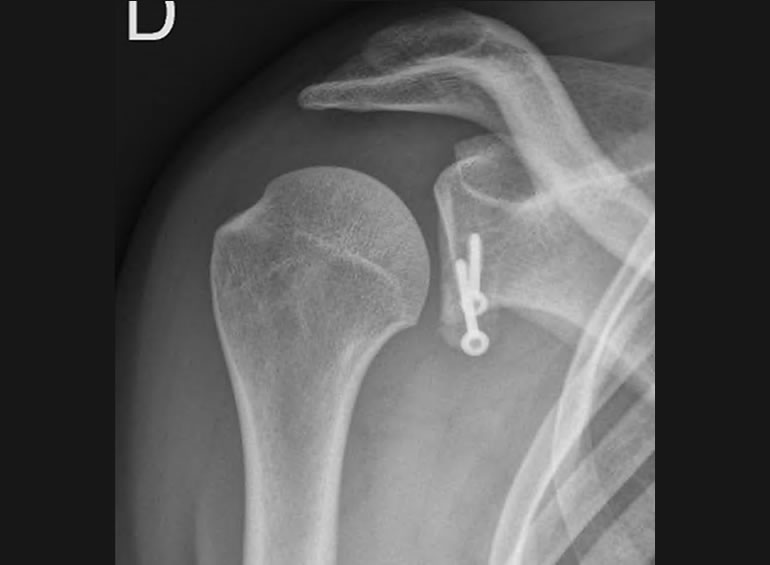

Desde el año 2015, al regresar de mi formación como subespecialista en Francia, estoy 100% dedicado al tratamiento de pacientes con lesiones traumáticas, degenerativas y deportivas de Hombro y Codo. Dividiendo mi practica clínica en pacientes con accidentes o secuelas en el Hospital Clínico Mutual de Seguridad CChC y a pacientes privados con lesiones traumáticas deportivas o domésticas y lesiones degenerativas en Clínica Alemana de Santiago.

Tras un accidente automovilístico de alto impacto con una serie de secuelas físicas, entre ellas la destrucción de mi codo quede con un brazo sin movimiento. Comencé la búsqueda de opiniones médicas para recuperar mi movilidad perdida y soñando volver a hacer algo tan sencillo como tocar mi cara, en esta búsqueda conocí al Dr Reinares quien me dio una esperanza con la cirugía de Protesis de Codo. Me sometí a dicha cirugía en el año 2016 de la que obtuve maravillosos resultados, recupere mi movilidad tan anhelada que me ha permitido hasta el dia de hoy realizar todas las actividades de mi vida diaria, Tremendamente agradecida de este gran profesional